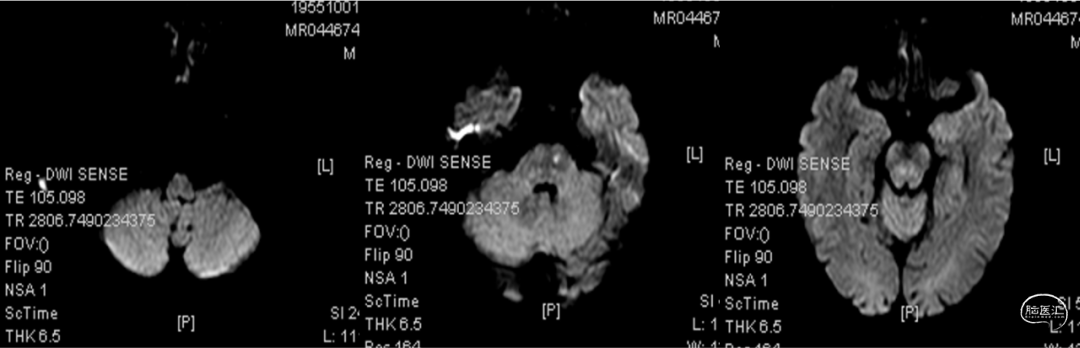

颅脑MRI+MRA+DWI提示:

1. 脑干左侧腔隙性脑梗塞(急性期);左侧基底节区、双侧半卵圆中心腔隙性脑梗塞;

2. 脑白质缺血、轻度脑萎缩;

3. 双侧上颌窦、筛窦粘膜增厚;

4. 脑动脉硬化改变,双侧椎动脉V4段、基底动脉及左侧大脑后动脉纤细;右侧大脑前动脉A1段未见显示。